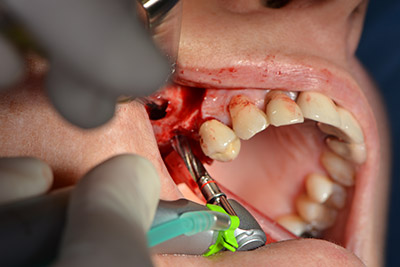

En el siguiente paso se efectúa la elevación del suelo del seno maxilar, a la vez que se coloca el implante. Para la fenestración lateral de la pared del seno maxilar Implantmed también cuenta con un ajuste predefinido en la primera posición.

La ventana se crea a una velocidad de 35.000 rpm y, a continuación, la membrana de Schneider se prepara en sentido craneal (figuras 13 a 14).

Acto seguido, se coloca el implante y se estructura el hueso. Dado el tamaño del aumento, en el caso que nos ocupa se utilizó hueso autógeno, que había surgido como virutas de fresado en el implante 16 y en la fenestración 14 y se había recogido con un colector óseo, y se combinó con material de reemplazo óseo.